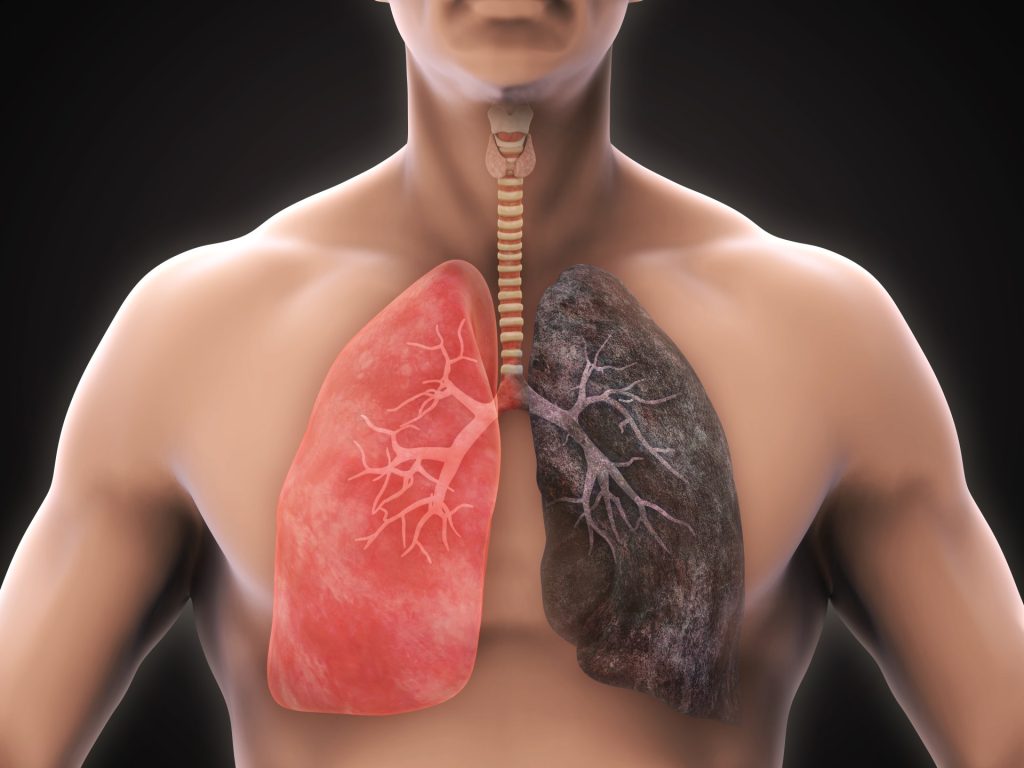

كشفت دراسة حديثة أن حتى التدخين المحدود يمكن أن يشكل خطرًا كبيرًا على صحة القلب والأوعية الدموية، مما يزيد من احتمالية الإصابة بأمراض القلب والسكتات الدماغية والوفاة. أظهرت الأبحاث أن تدخين عدد قليل من السجائر يوميًا لا يوفر أي حماية صحية، بل على العكس، يزيد من المخاطر بشكل ملحوظ. تأتي هذه النتائج لتؤكد على أهمية الإقلاع عن التدخين بشكل كامل.

أظهرت الدراسة أن الأشخاص الذين يدخنون ما بين سيجارتين إلى خمس سجائر يوميًا يواجهون زيادة بنسبة 50% في خطر الإصابة بأمراض القلب مقارنة بغير المدخنين. بالإضافة إلى ذلك، ارتفعت احتمالات الوفاة لديهم بنسبة 60%. هذه الزيادة في المخاطر تعتبر كبيرة جدًا، حتى بالنسبة لكميات صغيرة من التدخين.

على الرغم من الأضرار التي يسببها التدخين، تشير الدراسة إلى أن الإقلاع عنه يمكن أن يقلل بشكل كبير من المخاطر الصحية. أظهرت النتائج أن درجة الخطورة تتراجع بشكل ملحوظ بعد 10 سنوات من الإقلاع عن التدخين. ومع ذلك، فإن أضرار التدخين على الصحة يمكن أن تستمر حتى 30 عامًا بعد الإقلاع.